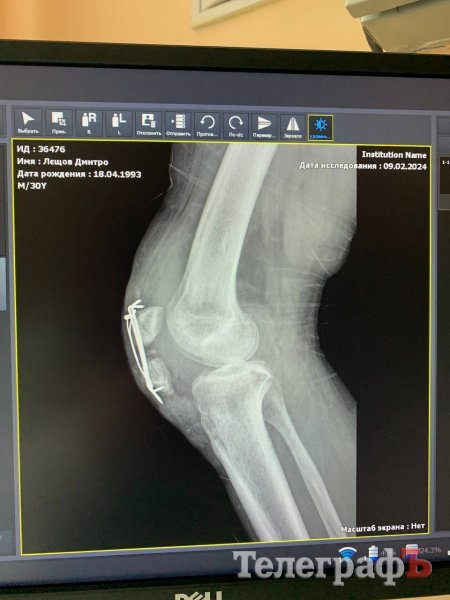

У військового була зламана рука, важкотравмований колінний суглоб, розірване коліно, серйозна травма голови.

За рік — вісім операцій, і потрібна ще одна

За цей час чоловік пройшов уже вісім оперативних втручань, і зараз йому знову потрібна операція.